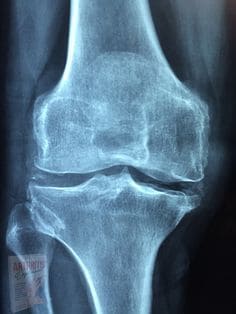

삶의 질을 저하시키는 원인중 하나로 손꼽히는 퇴행성 관절염!

퇴행성 관절염이 오면 우울해지기도 하고 움직이고 생활하는데 큰 불편감을 느끼기도 합니다.